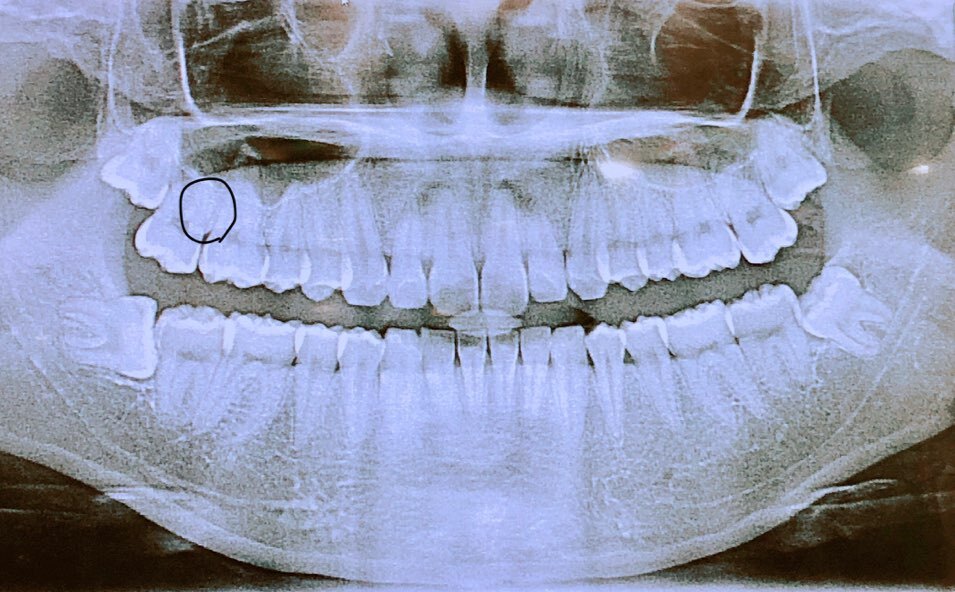

위 사진은 실제로 제 치아사진입니다. 윗 사랑니들은 나름 일자로 잘 나있으나 사진으로 왼쪽치아는 누워있는게 보이시죠? 이렇게 누워있으면 옆에 어금니 치아를 밀어내서 치열이 엉망이 된다고 합니다. 그래서 뽑아주는게 좋다고 합니다.

사랑니 주위에 염증이 발생했거나 통증, 두통을 느끼거나 충치가 많이 진행된 경우에는 꼭 뽑아야하고 이 경우가 아니더라도 기울거나 누워있는 경우에도 발치를 하는게 좋다고 합니다.

비스듬하게 누워있거나 완전 매복된 경우에는 잇몸을 절개해 뼈를 일부 갈아낸 후 치아를 조각내어 적출하기도 합니다.